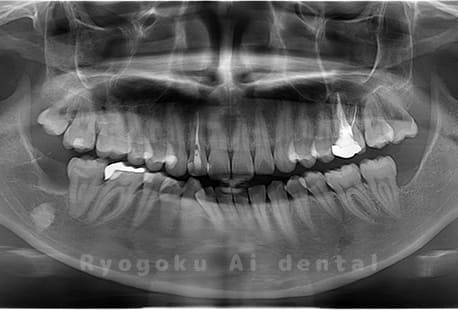

水平埋伏の親知らず

歯茎の中で完全に横に生えてしまうタイプです。

この親知らずを水平埋伏智歯と言います。このタイプはほとんどが下顎のケースです。真横に生えているので抜歯の際は難易度が高く2~3つに砕いて分けて抜歯をします。